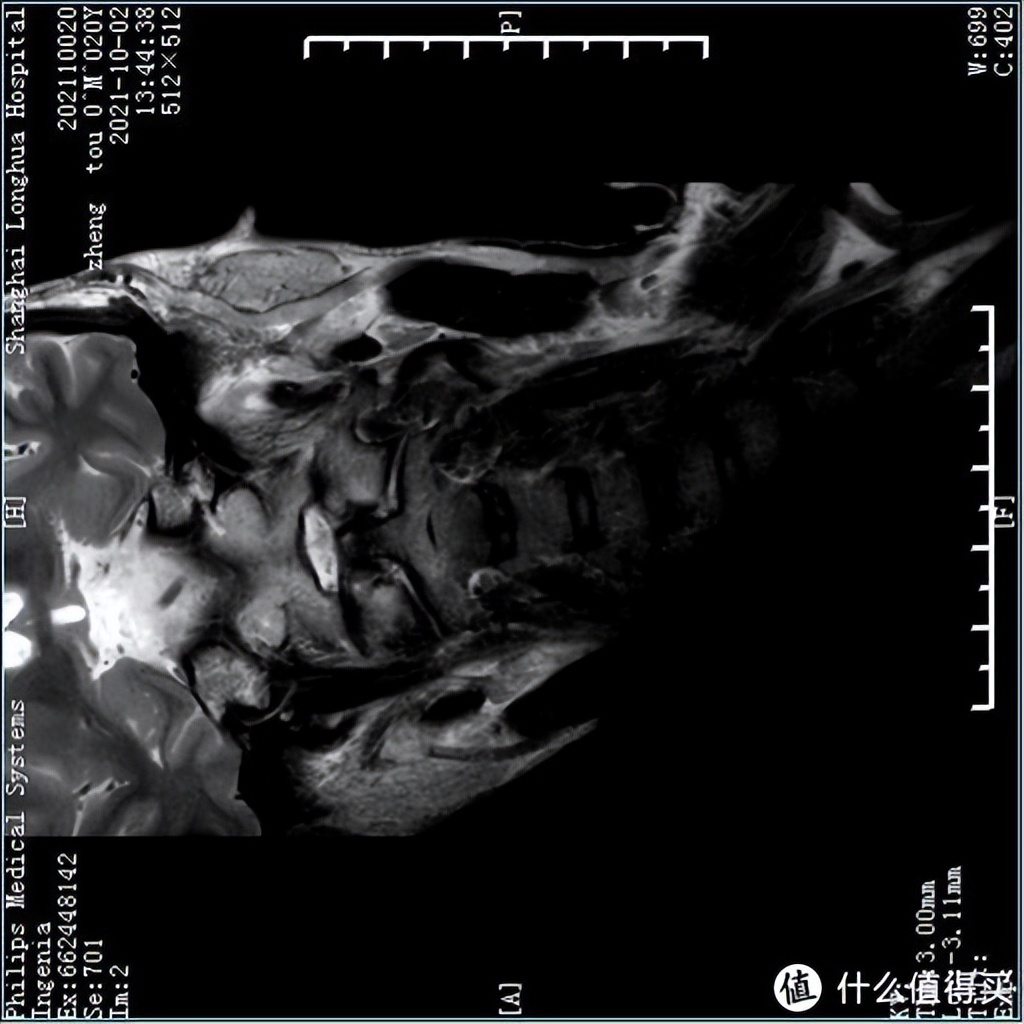

为了看到枕着不同枕头的状态下,颈椎内部结构会怎么改变,我还特意来到放射科,麻烦值班的兄弟给做了16组MRI成像。也感谢志愿者的付出。

首先让志愿者用仰卧位和侧卧位,无枕头的状态下拍摄了颈椎MRI,为了让人看明白,我特意把颈椎横过来摆到正常睡姿的体位。

仰卧位颈椎MRI: 不枕枕头的情况下,因为MRI机器本身有个固定器,头部还是处于比较合适的中立位,志愿者的上颈段椎间盘出现一定程度的退变,曲度略微反曲

侧卧位颈椎MRI: 为了看到侧卧的颈椎结构,我们用了一些小技巧,让机器略微识别出来了大致轮廓,尽管如此,下侧边缘还是有些模糊。但可看到侧卧位,因为没有枕头,头部往下掉,颈椎处于左右失衡的状态。

各种枕头下的MRI详细解读,我会专门出一期视频,现在还没有剪辑好,大家感兴趣的话可以点个收藏,点个追更,这两周就会有重磅测评结果发布~